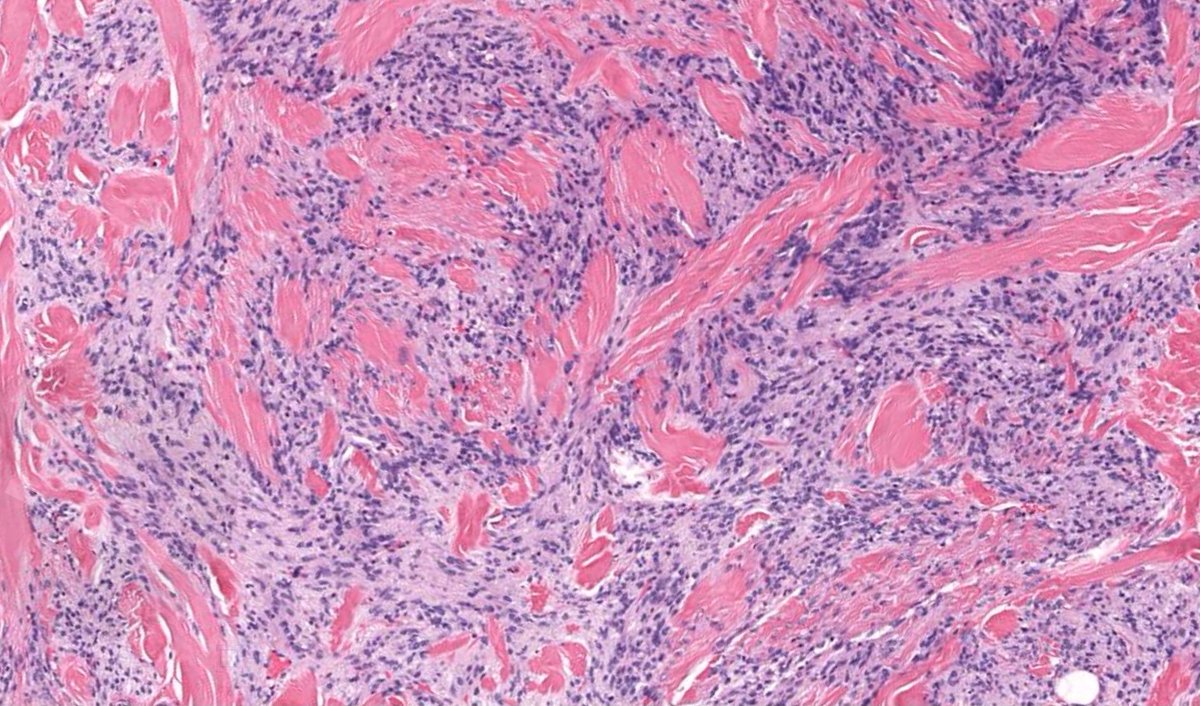

60 yo man with 2 cm breast mass. One of the BEST examples ever! Can you make diagnosis from one pic, or is it #TooCloseToDiagnose? Digital slide: kikoxp.com/posts/4600. Answer ✅ youtube.com/watch?v=eLmPGd… #pathologists #pathology #pathTwitter #BSTpath #breastpath

60 yo man with 2 cm breast mass. One of the BEST examples ever!

Can you make diagnosis from one pic, or is it #TooCloseToDiagnose?

Digital slide: kikoxp.com/posts/4600.

Answer ✅ youtube.com/watch?v=eLmPGd…

#pathologists #pathology #pathTwitter #BSTpath #breastpath